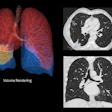

CT is ideally suited for characterizing and diagnosing both conditions, which share common cardiovascular and metabolic risk factors, Puchner explained.

The study aimed to determine the association of NAFLD with the presence of advanced high-risk coronary atherosclerotic plaque as assessed by coronary CT angiography (CCTA).

Positive remodeling was defined using the threshold of 1.1 for the maximal diameter of the vessel at the plaque over the diameter of the proximal and distal normal vessel reference (A). Low HU plaque consisted of the mean HU number within three regions of interest less than 30 HU (B). The napkin-ring sign is a ringlike peripheral higher attenuation surrounding a central core of low attenuation of a noncalcified coronary plaque (C). Spotty calcium was defined as calcified plaque with a maximum diameter less than 3 mm in any direction, length of the calcification less than 1.5 times the vessel diameter, and width of the calcification less than two-thirds of the vessel diameter (D). Image courtesy of Dr. Stefan Puchner.NAFLD was defined as the presence of hepatic steatosis on noncontrast CT without evidence of clinical liver disease, liver cirrhosis, and alcohol abuse, Puchner said.